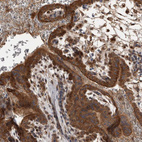

Immunohistochemical staining of human kidney, placenta, rectum and tonsil using Anti-DARS2 antibody HPA026506 (A) shows similar protein distribution across tissues to independent antibody HPA026528 (B).